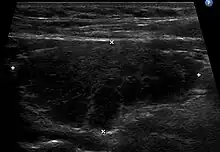

Ultrasound imaging of the thyroid gland (right lobe longitudinal) in a person with Hashimoto thyroiditis

Ultrasound imaging of the thyroid showing Hashimoto's thyroiditis

When patients have normal laboratory values but symptoms of autoimmune thyroiditis, ultrasound plays a role in diagnosis.[16] Images obtained with ultrasound can evaluate the size of the thyroid and further support the diagnosis of autoimmune thyroiditis, reveal the presence of nodules, or provide clues to the diagnosis of other thyroid conditions.[16]